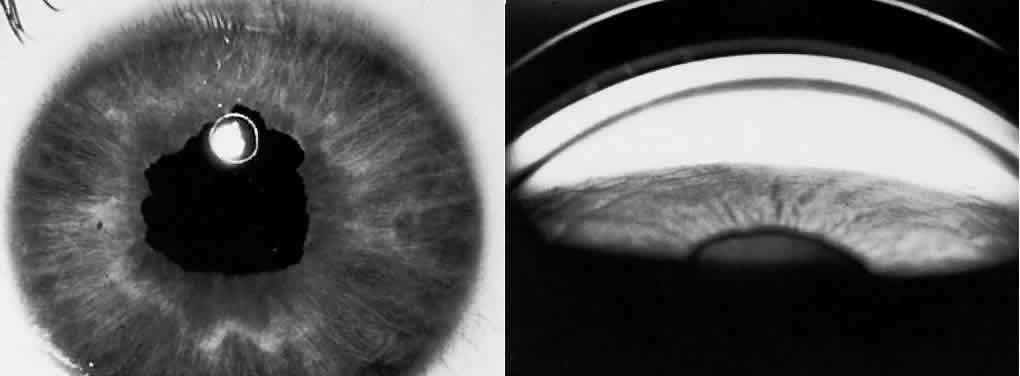

A syndrome of primary glaucoma associated with iridotrabecular dysgenesis and ectropion uveae has been described.34 In these patients, the iris pigment epithelium proliferates onto the anterior iris stroma in utero so that congenital ectropion uveae is present (Fig. 2). Glaucoma may be present in infancy or may develop later in life. Histologically, the central corneal stroma is normal; however, there is posterior embryotoxin (prominence and anterior displacement of Schwalbe's ring) with iris processes. Migration and hyerplasia of the pigment epithelium onto the anterior iris surface is accompanied by endothelialization of the iris surface peripheral to the area where pigment epithelium is present. Angle closure with iris adherent to a normally differentiated trabecular meshwork also is seen. The iris stroma is hypoplastic. The relation of this syndrome to the anterior chamber cleavage syndromes and to the iridocorneal endothelial (ICE) syndrome has not been established. This syndrome may bridge the groups of disorders characterized in Table 1 as secondary to abnormal crest cell migration and proliferation.

Fig. 2. Left, Slit-lamp photograph of congenital ectropion uveae. Right, Gonioscopic appearance of dysgenesis of filtration angle in congenital ectropion uveae. (Dowling JL Jr, Albert DM, Nelson LB, et al: Primary glaucoma associated with iridotrabecular dysgenesis and ectropion uveae. Ophthalmology 92:912, 1985)